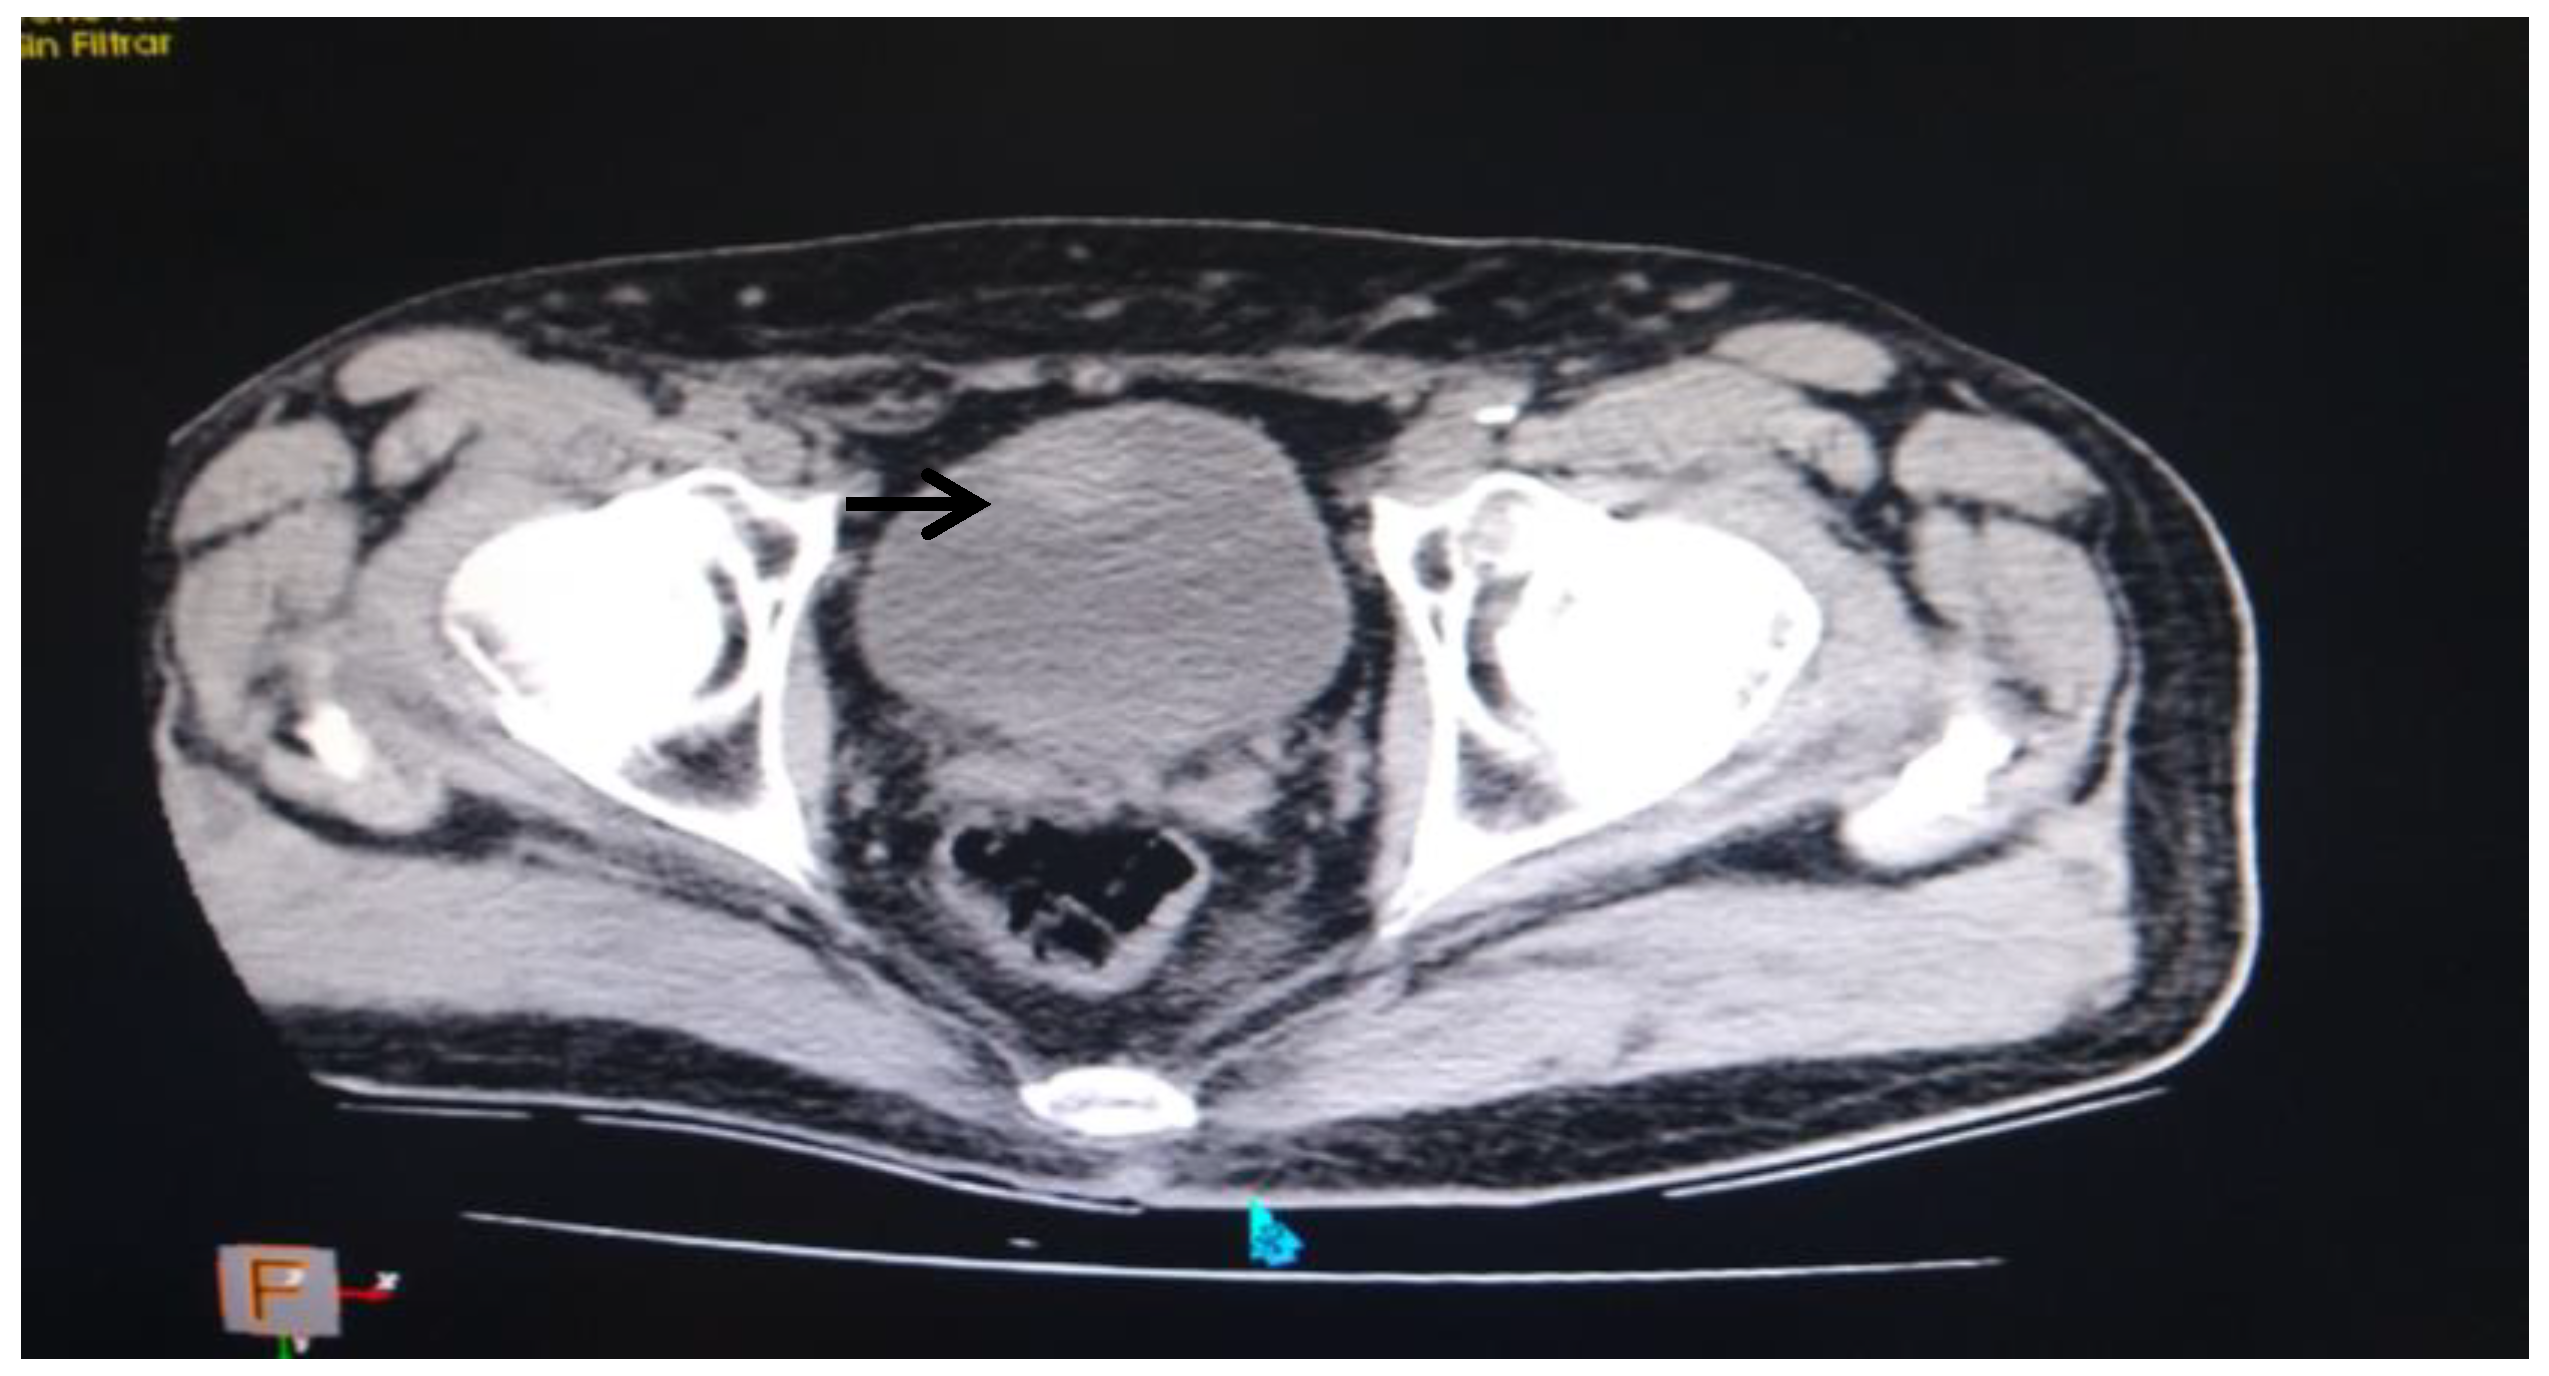

- ✓ Estudios imagenológicos: